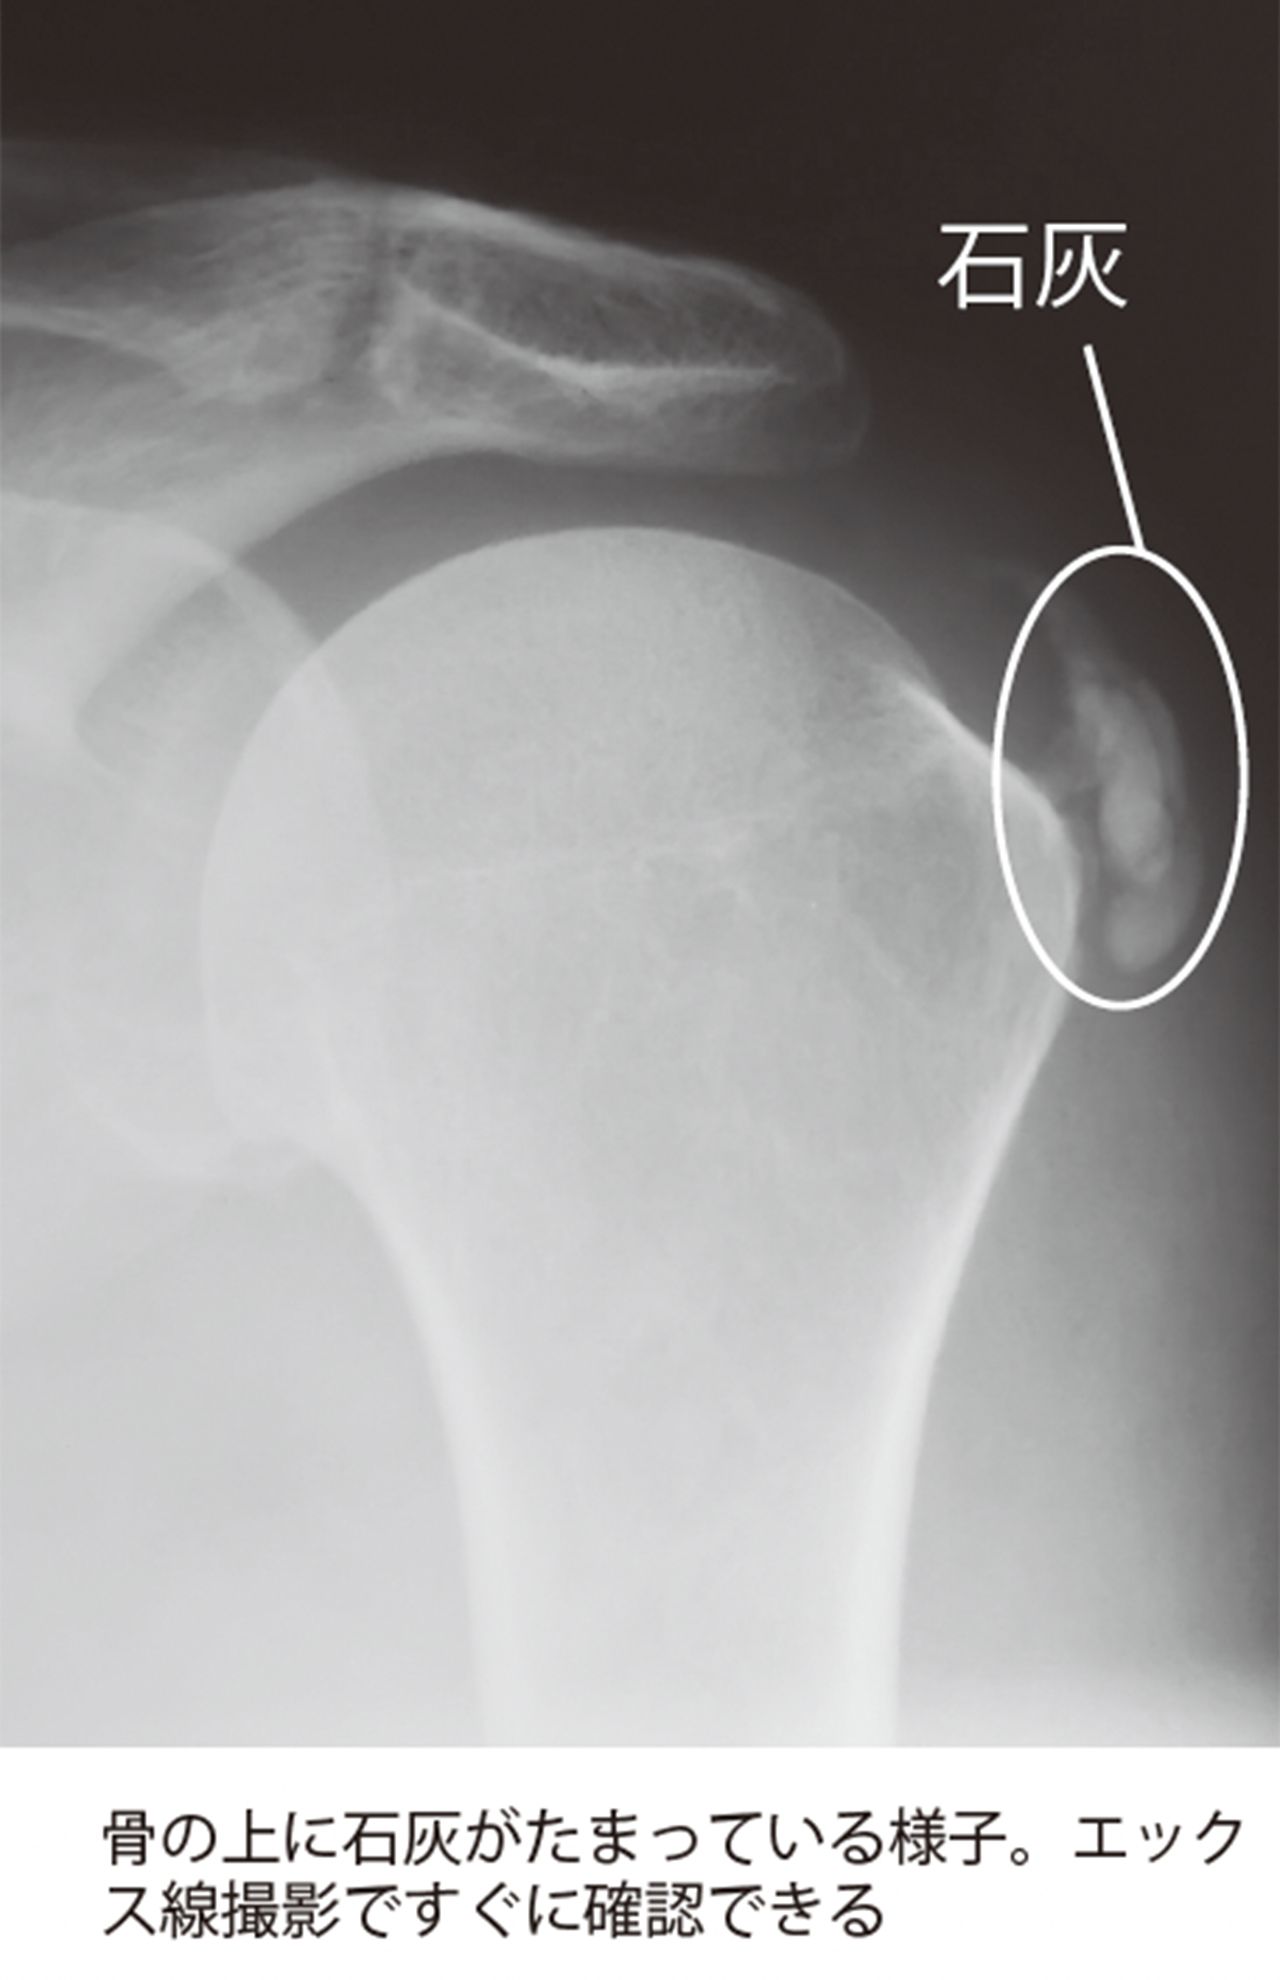

ライフ 2024/10/22 突然の激痛に医師が告げた「骨に“石”ができています」五十肩と勘違いしがちな中年女性に要注意の“病” シニア健康女性ホルモン医師高齢者更年期障害 印刷 【写真】骨の上に石灰がたまっている様子を撮影したレントゲン 骨の上に石灰がたまっている様子。エックス線撮影ですぐに確認できる 治療法は石灰に直接ステロイド剤を注入する方法などがある。患者数も多い病状のため、ほかにもさまざまな治療法が導入されだしている 治療法は石灰に直接ステロイド剤を注入する方法などがある。患者数も多い病状のため、ほかにもさまざまな治療法が導入されだしている※写真はイメージです ※写真はイメージです 広告を見ると、続きの写真を見ることが可能になります 続きの写真を見る ページをリロードする 記事詳細を見る facebook いいね X ポスト LINE はてなブックマークに追加 健康の記事一覧を見る タレコミを投稿する 今日の運勢を無料で見る コピーしました